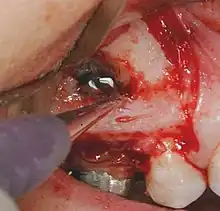

Chirurgie apicale: Principes généraux.

- On obtient une anesthésie convenable.

- On choisit un lambeau chirurgical approprié, et on envisage une réclinaison mucopériostée, traumatisante a minima.

- On pratique une ostéotomie en regard de la lésion, on suit la procédure appropriée et le lambeau est replacé et suturé.